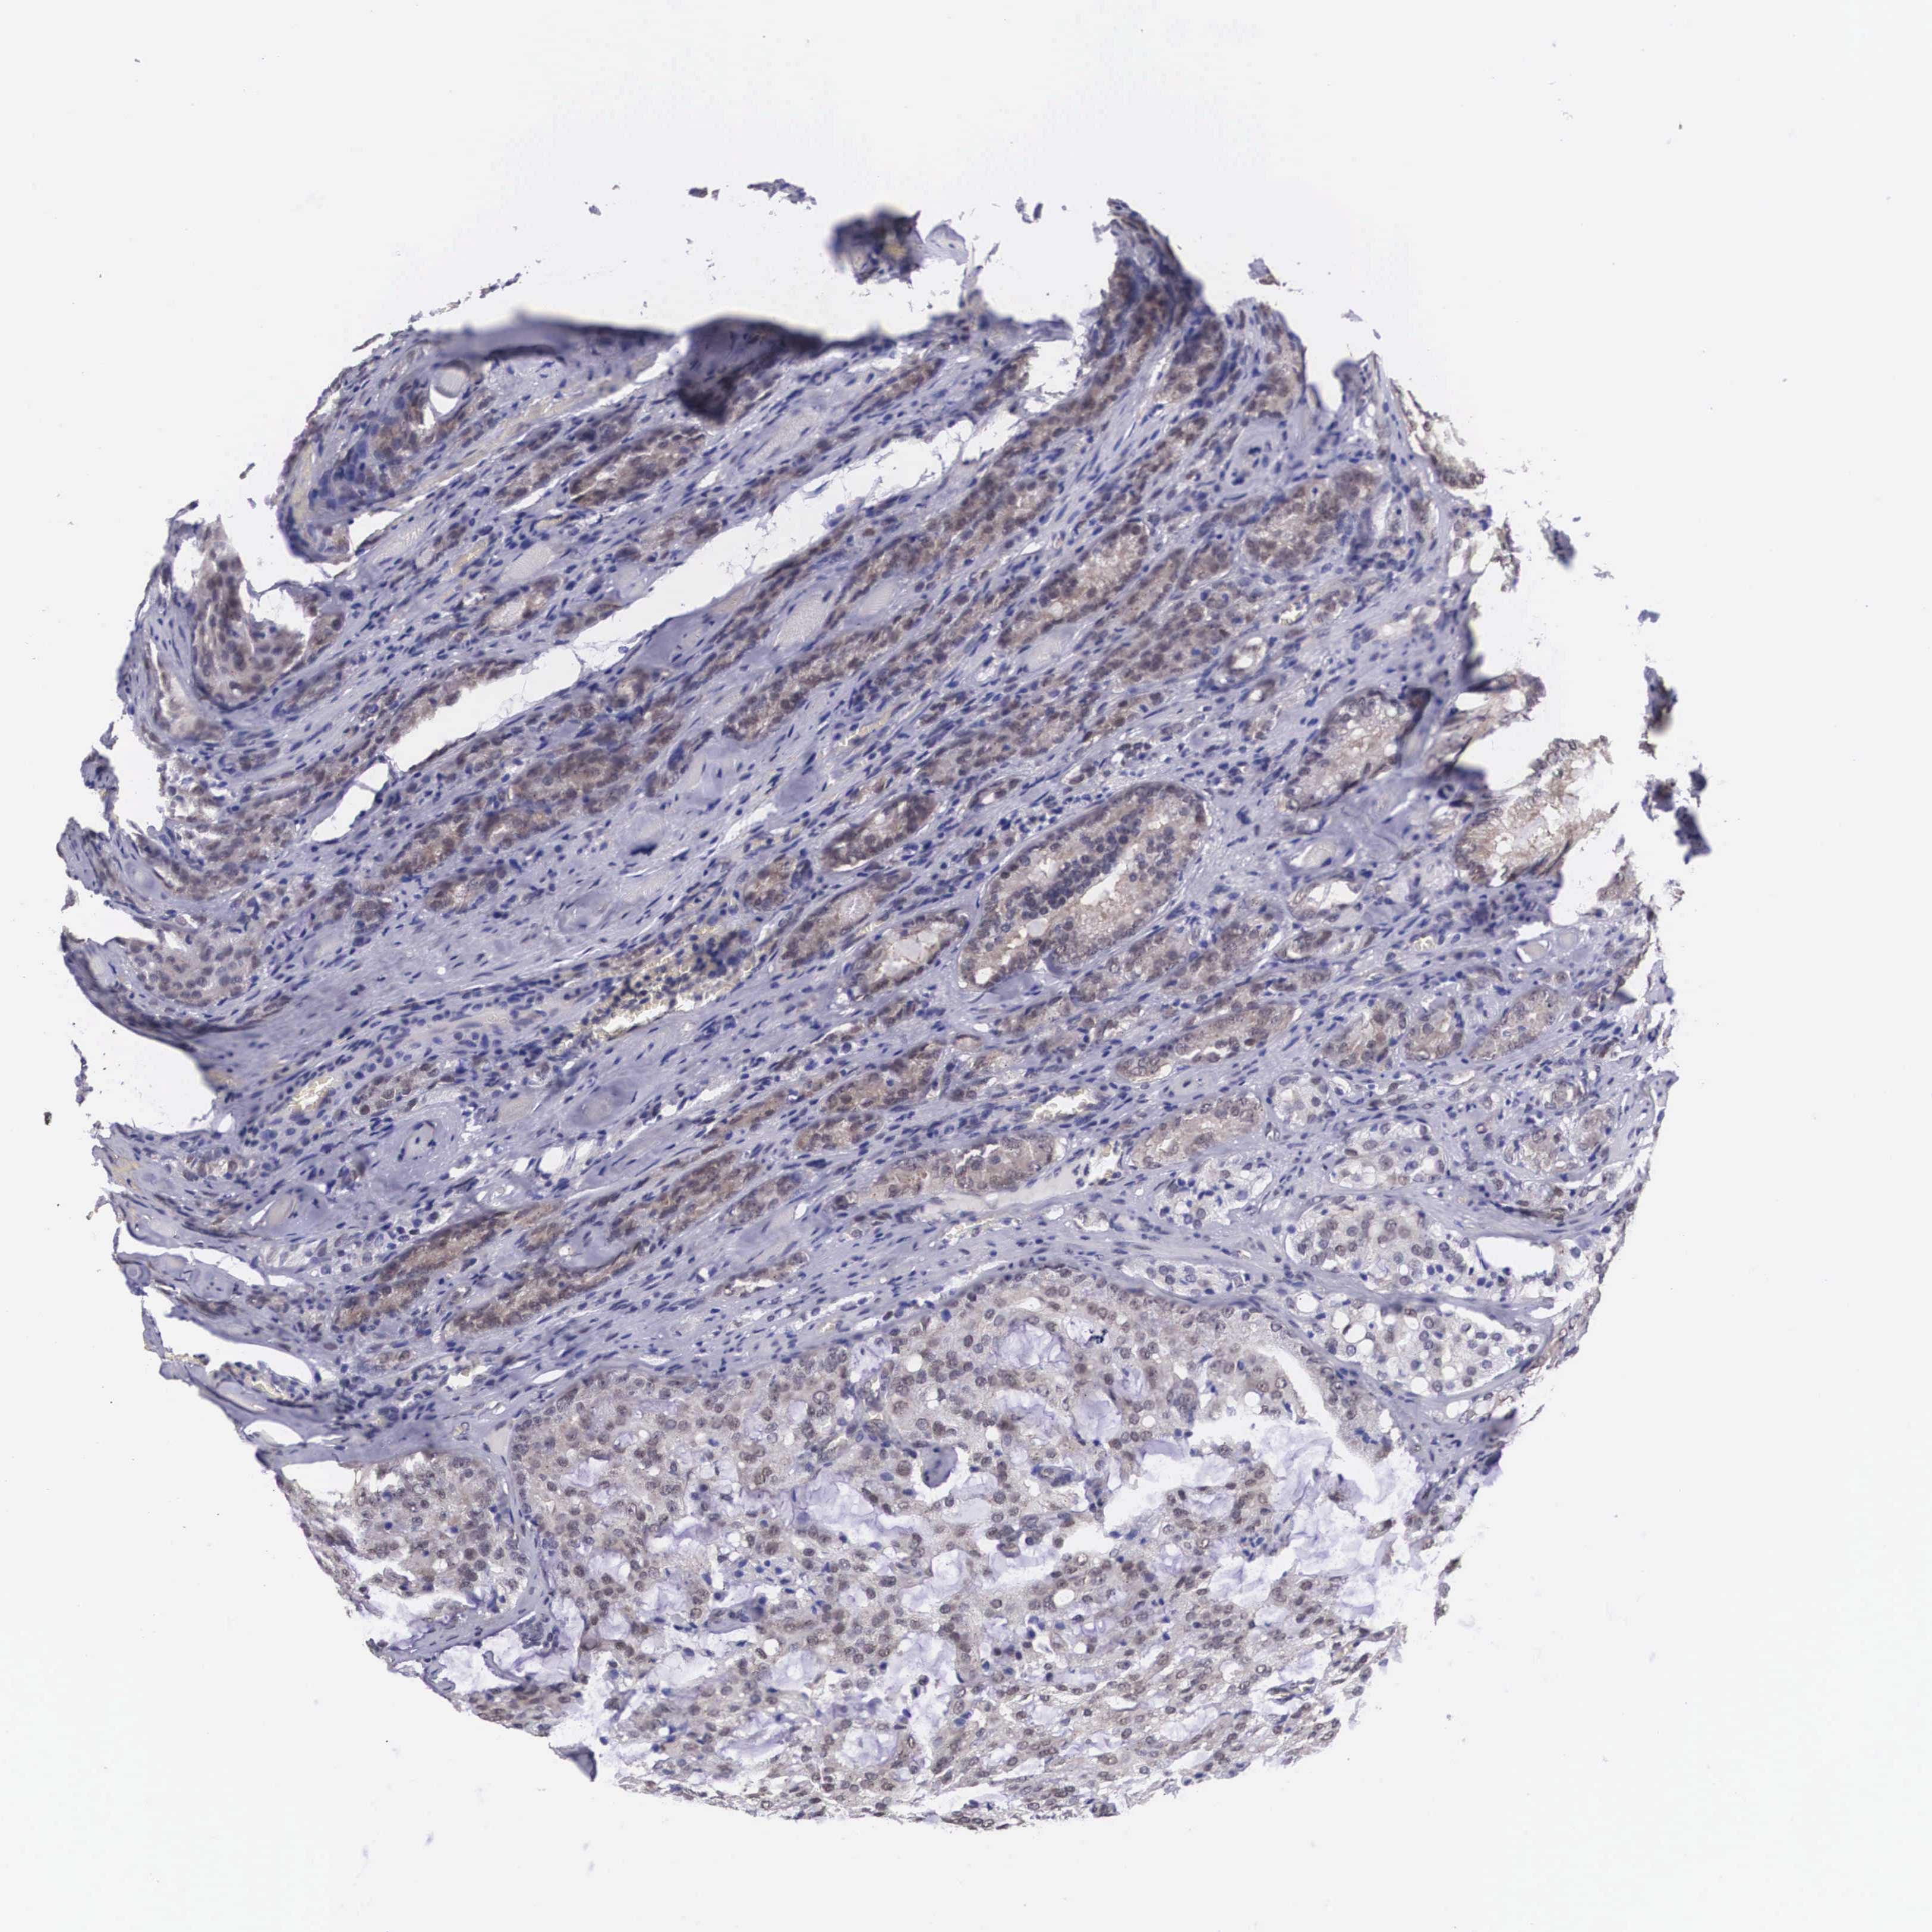

PROSTATE CANCER - Protein expressioni

A mouse-over function shows sample information and annotation data. Click on an image to view it in a full screen mode. Samples can be filtered based on level of antibody staining by selecting one or several of the following categories: high, medium, low and not detected. The assay and annotation is described here.

Note that samples used for immunohistochemistry by the Human Protein Atlas do not correspond to samples in the TCGA dataset.

Antibody stainingi

Antibody staining in the annotated cell types in the current human tissue is reported as not detected, low, medium, or high, based on conventional immunohistochemistry profiling in selected tissues. This score is based on the combination of the staining intensity and fraction of stained cells.

Each image is clickable and will lead to virtual microscopy that enables deeper exploration of all samples and also displays staining intensity scores, fraction scores and subcellular localization as well as patient and tissue information for each sample.

Antibody HPA000633

Staining

High

Medium

Low

Not detected

Intensity

Strong

Moderate

Weak

Negative

Quantity

>75%

75%-25%

<25%

None

Location

Nuclear

Cytoplasmic/membranous

Cytoplasmic/membranous,nuclear

Adenocarcinoma, Medium grade

Adenocarcinoma, Low grade

Adenocarcinoma, High grade